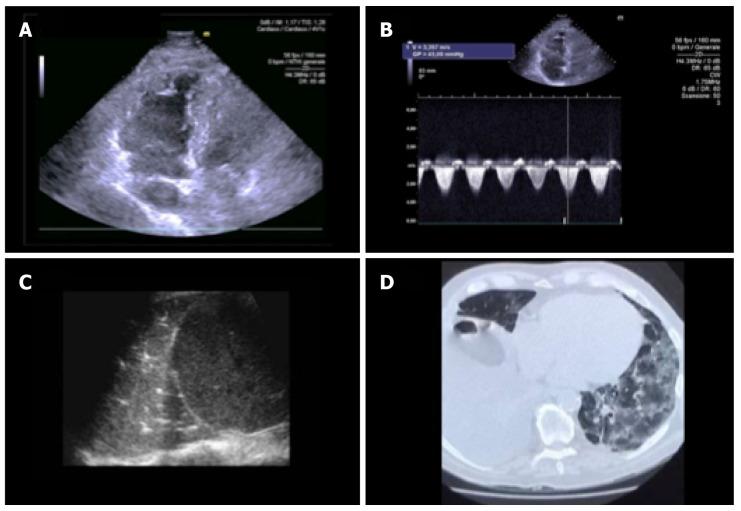

The integrated clinical, laboratory and ultrasound approach is essential for the diagnosis, evaluation and monitoring of the patient's therapy in coronavirus disease 2019 pneumonia. The ideal imaging approach in this context is not yet well defined. Chest X-ray is characterized by low sensitivity in identifying earlier lung changes. The "bedside" pulmonary ultrasound has an undeniable series of advantages in the patient at high infectious risk and can provide incremental data in the respiratory intensive care for the serial control of the individual patient as well as for the home delivery of the stabilized subjects. Pulmonary computed tomography shows high sensitivity but should not be routinely performed in all patients, because in the first 48 h it can be absolutely negative and in the late phase the imaging findings may not change the therapeutic approach. Echocardiography should be limited to patients with hemodynamic instability to assess ventricular function and pulmonary pressures.